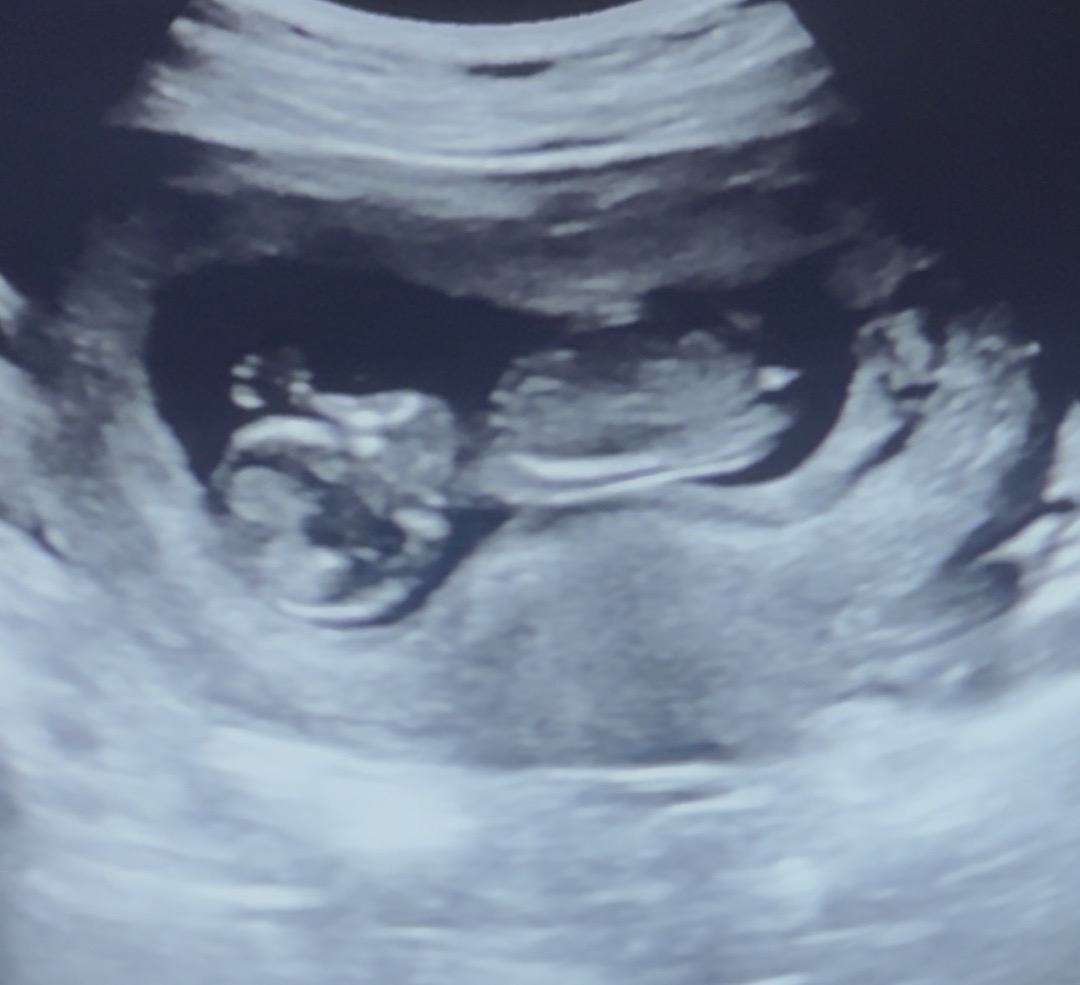

12주 2일 각도법 확인부탁드려요!!!

첫 임신이라 저는 아무리봐도 모르겠어요ㅠㅠ 각도법 확인 한 번 부탁드려요!!